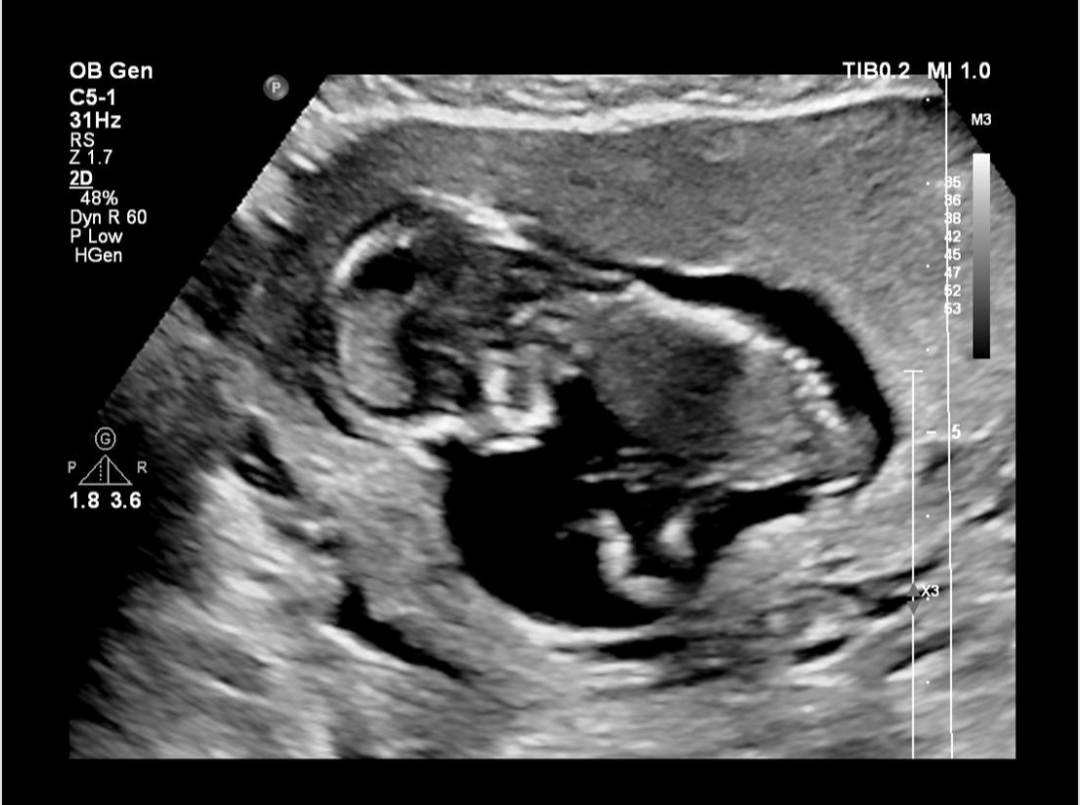

اینم عکسا بچه

Nb هم منظور بینی هست بنظرم

آره تیغه بینی

ببین اگر خدایی نکرده مسئله ای بود توی سونو مینوشت ک nb رویت نشد

ببین هیچی از nb ننوشته

درمورد nb در طی سال های اخیر کلا در سیستم نوین گزارش دهی nb از سونوگرافی سه ماهه اول حذف شده در آنومالی گزارش میگردد و برای همین گفته اند nb را وارد گزارش نکنید